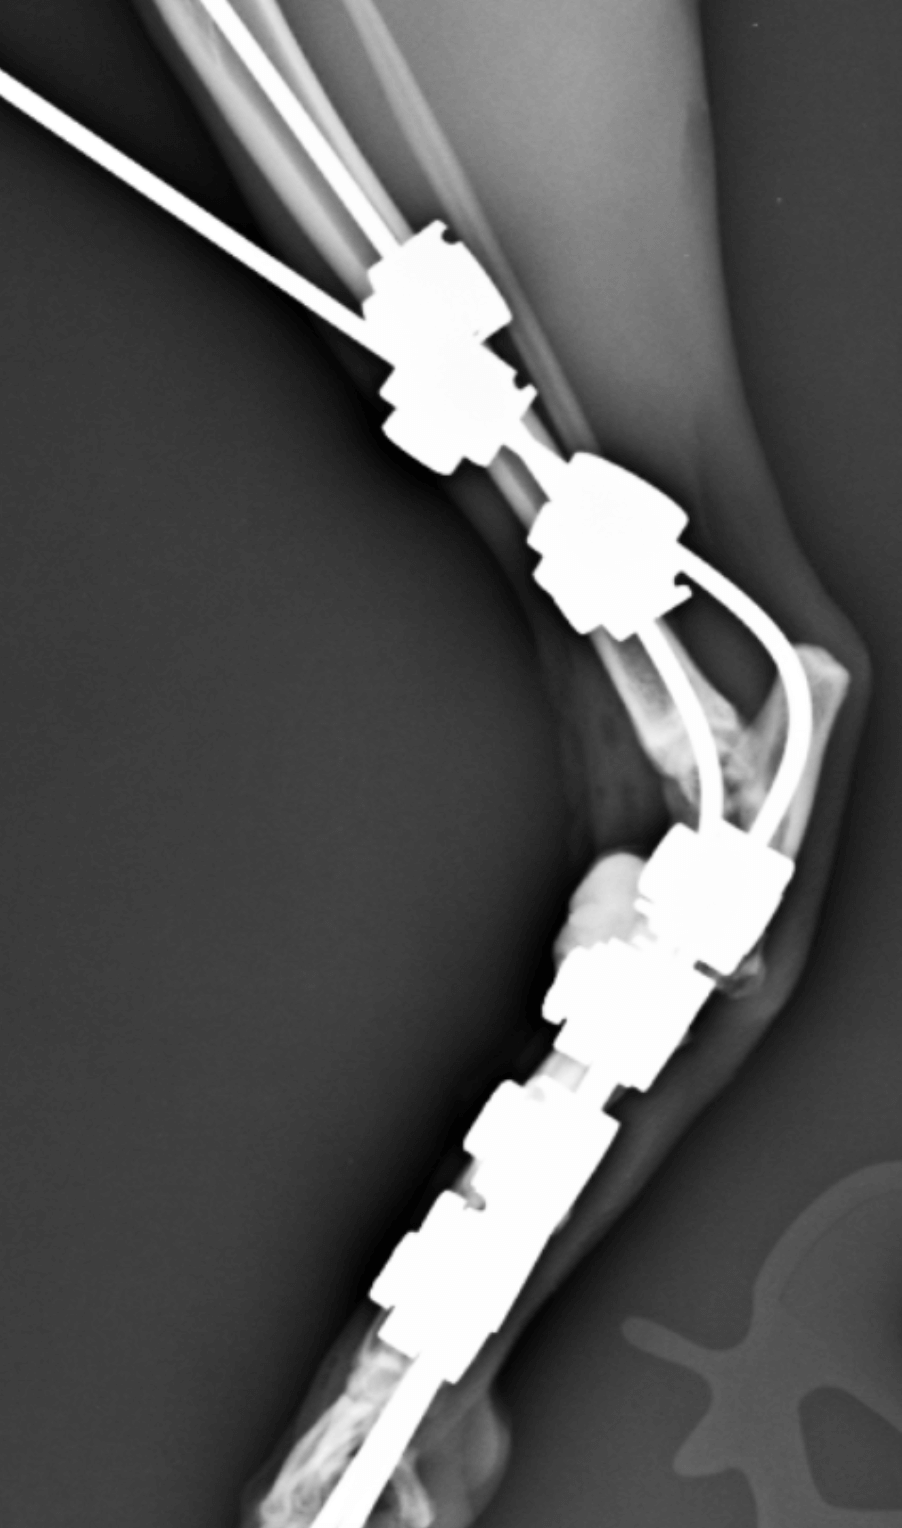

Arthrodèse du tarse chez Nahia avec sa luxation tarso-metatarsienne ouverte. Vue de profil